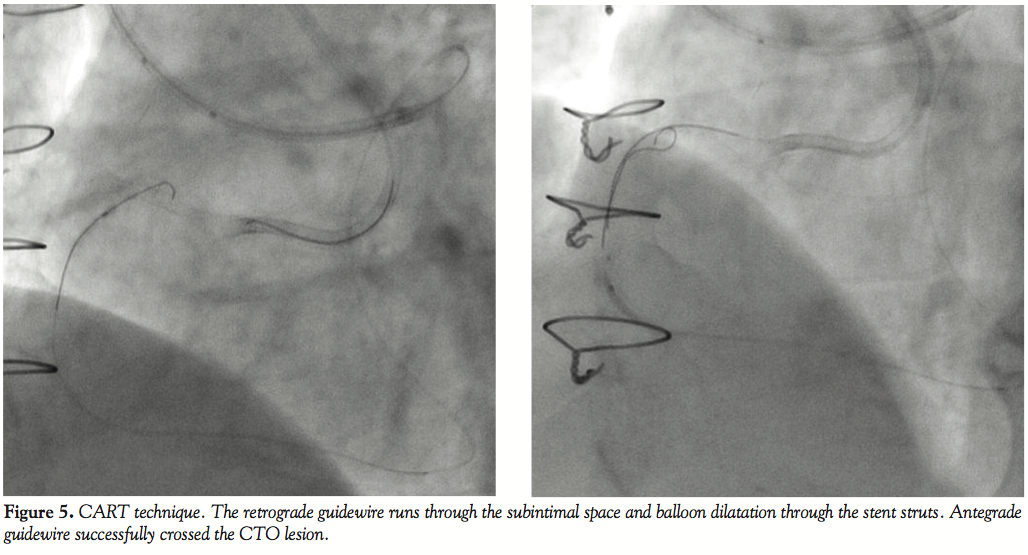

Fielder FC (Asahi Intecc Co. Ltd.) and advanced into the distal segment of the CTO (Figure 4). We attempted the antegrade approach by the kissing wire technique with an antegrade Conquest Pro guidewire and a retrograde Miracle 6 g guidewire (Asahi). However, both guidewires deviated into the subintimal space and could not cross the CTO because of obstruction by the stent. Therefore, we tried the controlled antegrade and retrograde subintimal tracking (CART) technique. A Fielder FC guidewire was advanced retrogradely into the subintimal space and a 1.25 x 10 mm Ryujin Plus OTW balloon (Terumo) was passed through the stent struts (Figure 5). The lesion was dilated with a Sprinter Legend 2.0 x 10 mm balloon (Medtronic), and the antegrade Conquest Pro guidewire (Asahi) successfully crossed the CTO to enter the true lumen (Figure 6). This guidewire was subsequently exchanged for a Runthrough hypercoat guidewire (Terumo) (Figure 7). Intravascular ultrasound confirmed that the wire had crossed the occlusion through the subintimal space by running along the outer border of the stent and had re-entered the distal true lumen as expected. Two Cypher stents (Cordis Corp.) were placed and expanded to 20 atm, including a 2.5 x 23 mm distal stent and a 3.0 x 33 mm proximal stent. The final angiogram revealed an excellent result (Figure 8). After the procedure, the patient was stable without elevation of enzymes. The 8-month follow-up angiogram showed no restenosis.

Problems that arise with the retrograde approach include difficulty in advancing the guidewire through the collateral channel, as well as subsequently crossing the CTO with the guidewire and devices. In the patient reported here, the stent previously implanted at the RCA ostium was angled toward a side branch on pre-procedural CTCA. Although the stent proximal to the mid segment of the CTO seemed to be inside the true lumen on the normal MIP view, the mid-to-distal part of the stent was found to be in a false lumen on the short axis view. Thus, the information obtained by pre-procedural CTCA was useful for deciding the therapeutic strategy. We predicted that a guidewire would not be able to enter the true lumen via the antegrade approach based on the CTCA findings, so we employed the retrograde approach via a septal collateral. Because the stent was implanted in a false lumen, we performed balloon dilatation of the subintimal space and stent struts and succeeded in advancing the guidewire by the CART technique after failure of the kissing wire technique and knuckle wire technique.

The CART technique is one of the most important skills for the retrograde approach. A subintimal dissection is created retrogradely, which allows the operator to limit extension of the dissection to the CTO portion.

When the retrograde guidewire enters a false lumen and penetrating the CTO is difficult, the CART8 and reverse CART9 techniques are widely used. Surmely et al8 reported 10 patients with CTO who were successfully treated by the CART technique. In this technique, a balloon is inserted retrogradely along a retrograde guidewire that lies in a false lumen and is inflated to expand the false lumen, after which an antegrade guidewire is advanced into the true lumen distal to the CTO via the expanded false lumen. Recently, the reverse CART technique has been reported, during which a balloon is inserted via the antegrade approach to expand the false lumen. After that, a retrograde guidewire is advanced.9 This technique is simple, but there is a risk of causing severe dissection.